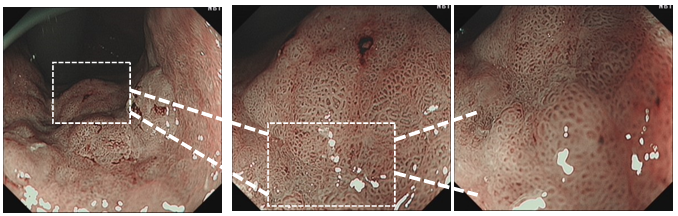

结合患者内镜检查病理活检,诊断考虑胃体小弯侧早期Ca(0-Ⅱb,中分化腺癌?),患者HP感染(+),同时有吸烟史,可考虑行ESD治疗。手术过程如图:首先应用海博刀沿着肿瘤边缘3~5 mm进行标记,而后予以标记点外缘2~3 mm与切开,完整剥除,创面血管予以热凝止血。

考虑病灶为胃体小弯侧黏膜内癌,手术不易暴露,ESD手术整块切除病变存在一定难度,容易穿孔,且该部位血供丰富,术中易发生出血,影响手术视野,手术过程中需保证黏膜下注射充分,得层次清晰,有助于病变的完全剥离,术中,在剥离肿物后发现一粗大血管,予以热活检钳及APC处理,术后处理好创面后,可放置胃管等措施,便于观察迟发性出血穿孔等情况。